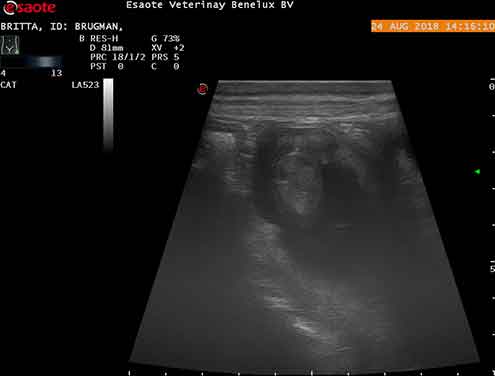

Britta van de Ramshoven

DOB: 23-09-2015 NHSB: 3019298, HD-A, ED vrij, JLPP N/N-vrij-, BNLJW '16, NLDJK '16, NLDK '17, NRC Showbokaal '17, MAG-test

DOB: 21-09-2018, 4 reuen en 4 teven.